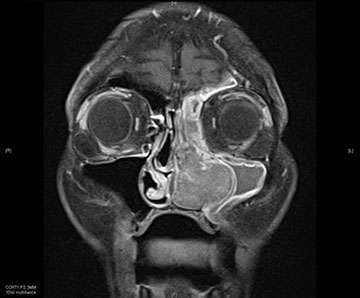

L’esthesioneuroblastome, également connu sous le nom de neuroblastome olfactif, est un cancer rare qui se manifeste dans le bulbe olfactive, la partie du cerveau qui interprète l’odeur. Les symptômes varient en fonction de l’emplacement et de l’étendue de la tumeur. Les symptômes les plus courants sont l’obstruction nasale, les saignements de nez, les maux de tête, les douleurs faciales et la diminution de l’odorat.

Les esthésioneuroblastomes sont traités chirurgicalement par chirurgie endoscopique endonasale et peuvent être suivis d’une radiothérapie ou d’une chimiothérapie.